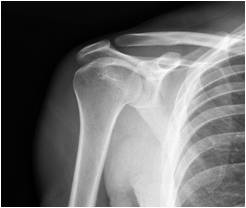

The shoulder is a ball and socket joint formed by the arm bone (humerus) and the shoulder blade (scapula).